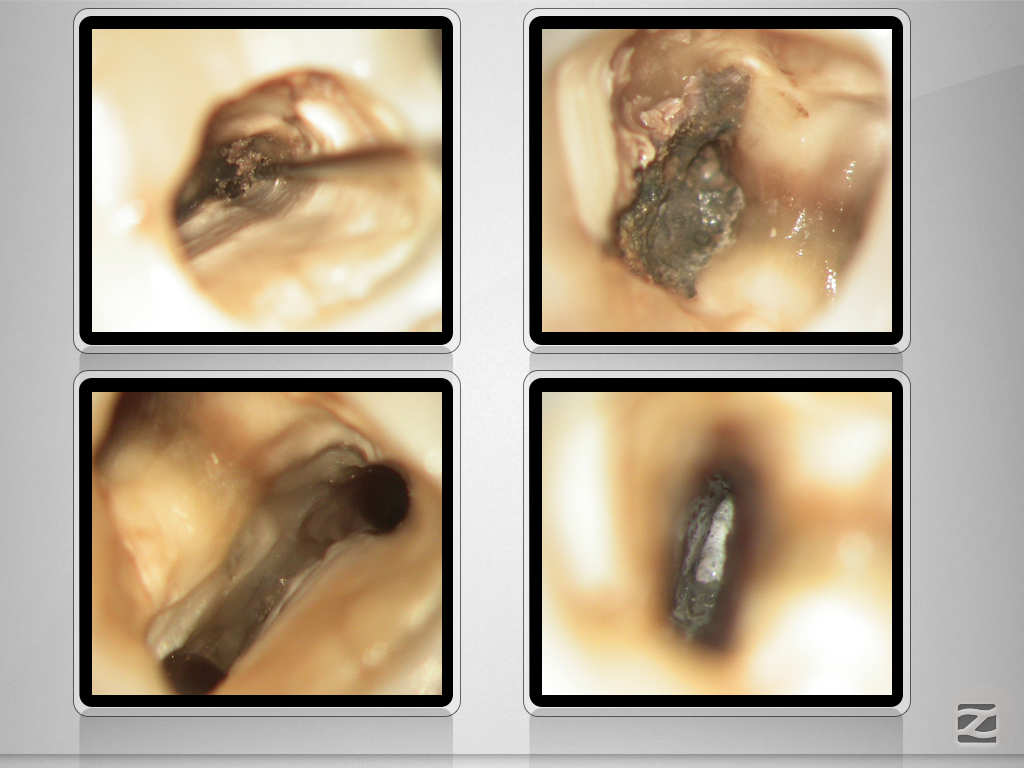

36D.008